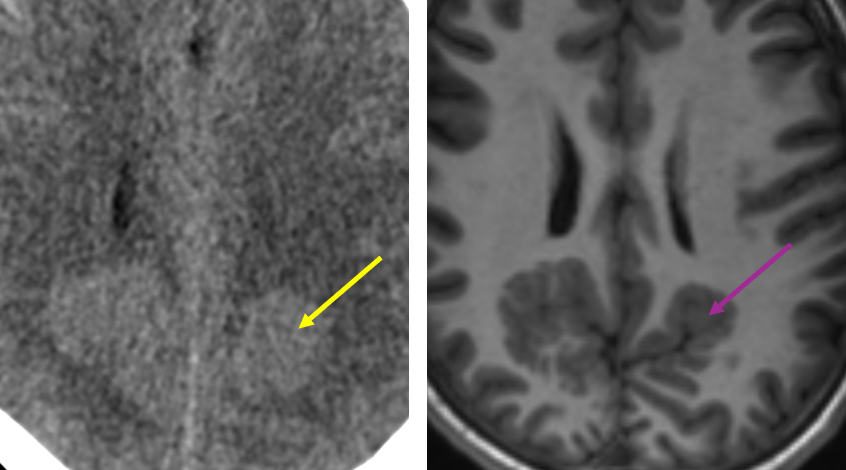

Tip of the day 💡: NF-1 related FASIs like to hide in the hippocampi. Definitely a review area! No seizures in this case. This weekend, trick and treat!